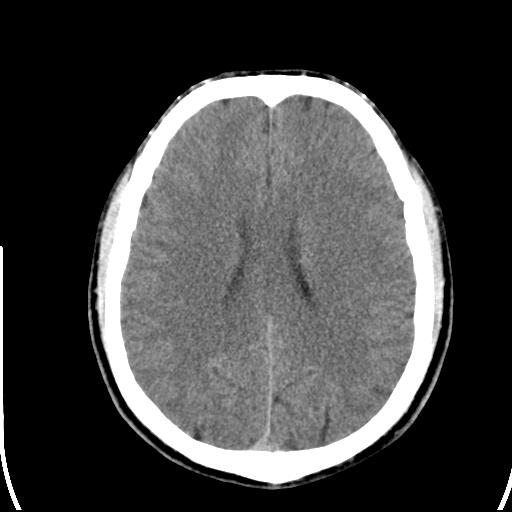

头皮下高密度结节影???临床上在老年男性比较常见。大家看看是什么?成因是? 本例患者,男性,51岁。外伤来诊。无染发史及发根植入史。

皮下钙化点

没见过,可能为毛囊钙化。

考虑钙化。